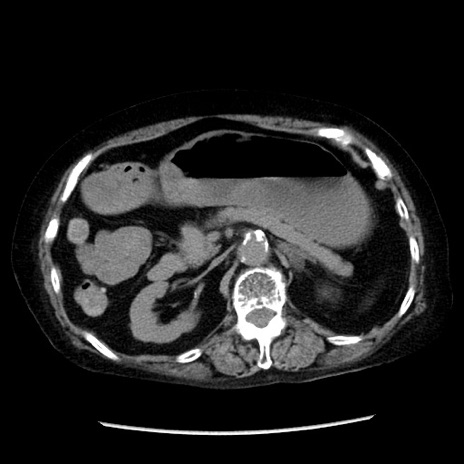

冠状断像

【症例】 90歳代女性

【主訴】 腹痛・嘔吐

【現病歴】今朝から左側腹部痛を認めた。 経過観察していたが、嘔吐を認めたため来院。

【既往歴】 子宮癌術後

【身体所見】 意識清明、BP 127/54mmHg、P 98bpm Sp02 95%(RA)、BT 35.8°C、腹部平坦・軟腸ぜん動音聴取良好、右下腹部圧痛(+) 反跳痛なし

【データ】WBC 9800、CRP 0.46